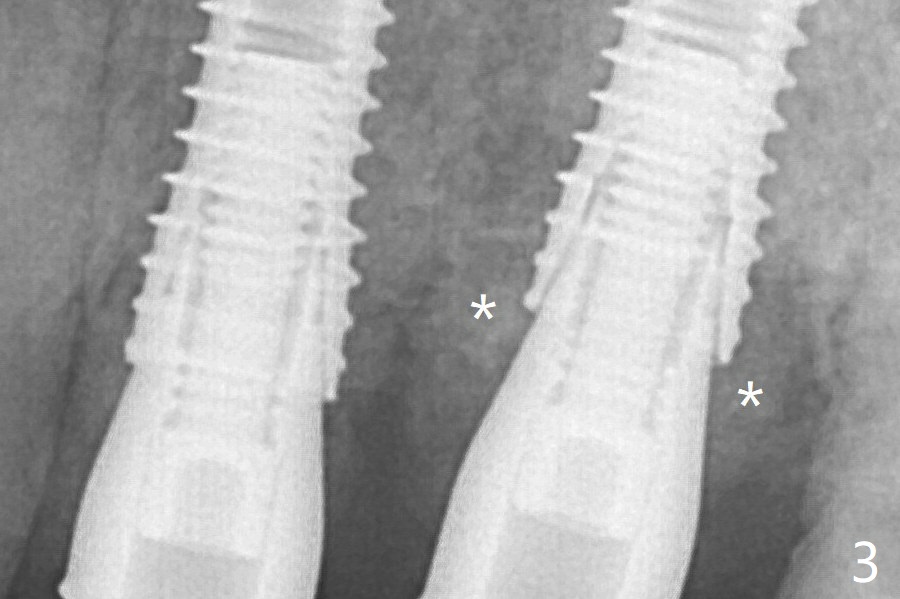

After correction of trajectory at #12 and 3 mm drill for 16 mm at the sites, two of 3.8x16 mm implant are placed with insertion torques of 35 and 15 Ncm, respectively (Fig.2). Before and after change into shorter abutments (4.5x4(4) and (5)), Vera Graft is placed (Fig.3 *). The allograft appears to have been incorporated into the host bone nearly 4 months postop (Fig.5).